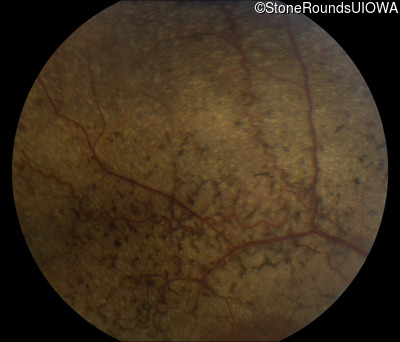

Fundus Photography - Right - 20/200 +1

Exemplar